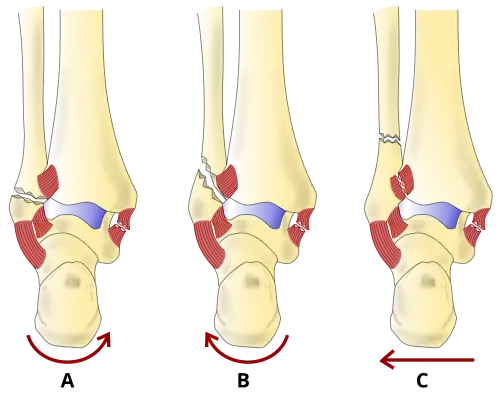

There are several classification schemes for ankle fractures. Out of the following, the Lauge-Hansen and Danis-Weber classification systems are most commonly used.[9]

- The Lauge-Hansen classification categorizes fractures based on the mechanism of the injury as it relates to the position of the foot and the deforming force (the most common type is supination-external rotation)

- The Danis-Weber classification categorizes ankle fractures by the level of the fracture of the distal fibula (type A = below the syndesmotic ligament, type B = at its level, type C = above the ligament), with use in assessing injury to the syndesmosis and the interosseous membrane